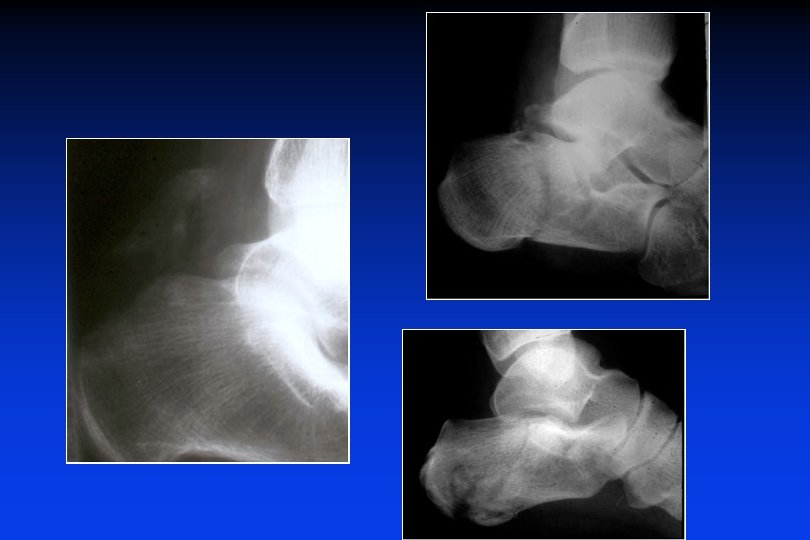

Rx grafie: Incidenza assiale retro-tibiale o dorsoplantare Sustentaculum tali Calcagno “in A. P. ” Fratture talamiche - parziali - totali

Caretteristiche delle linee di frattura talamiche viste di profilo Angolo di BÖEHLER Enfoncement vertical - horizontal

Caratteristiche delle fratture talamiche Affossamento orizzontale Angolo di BÖEHLER